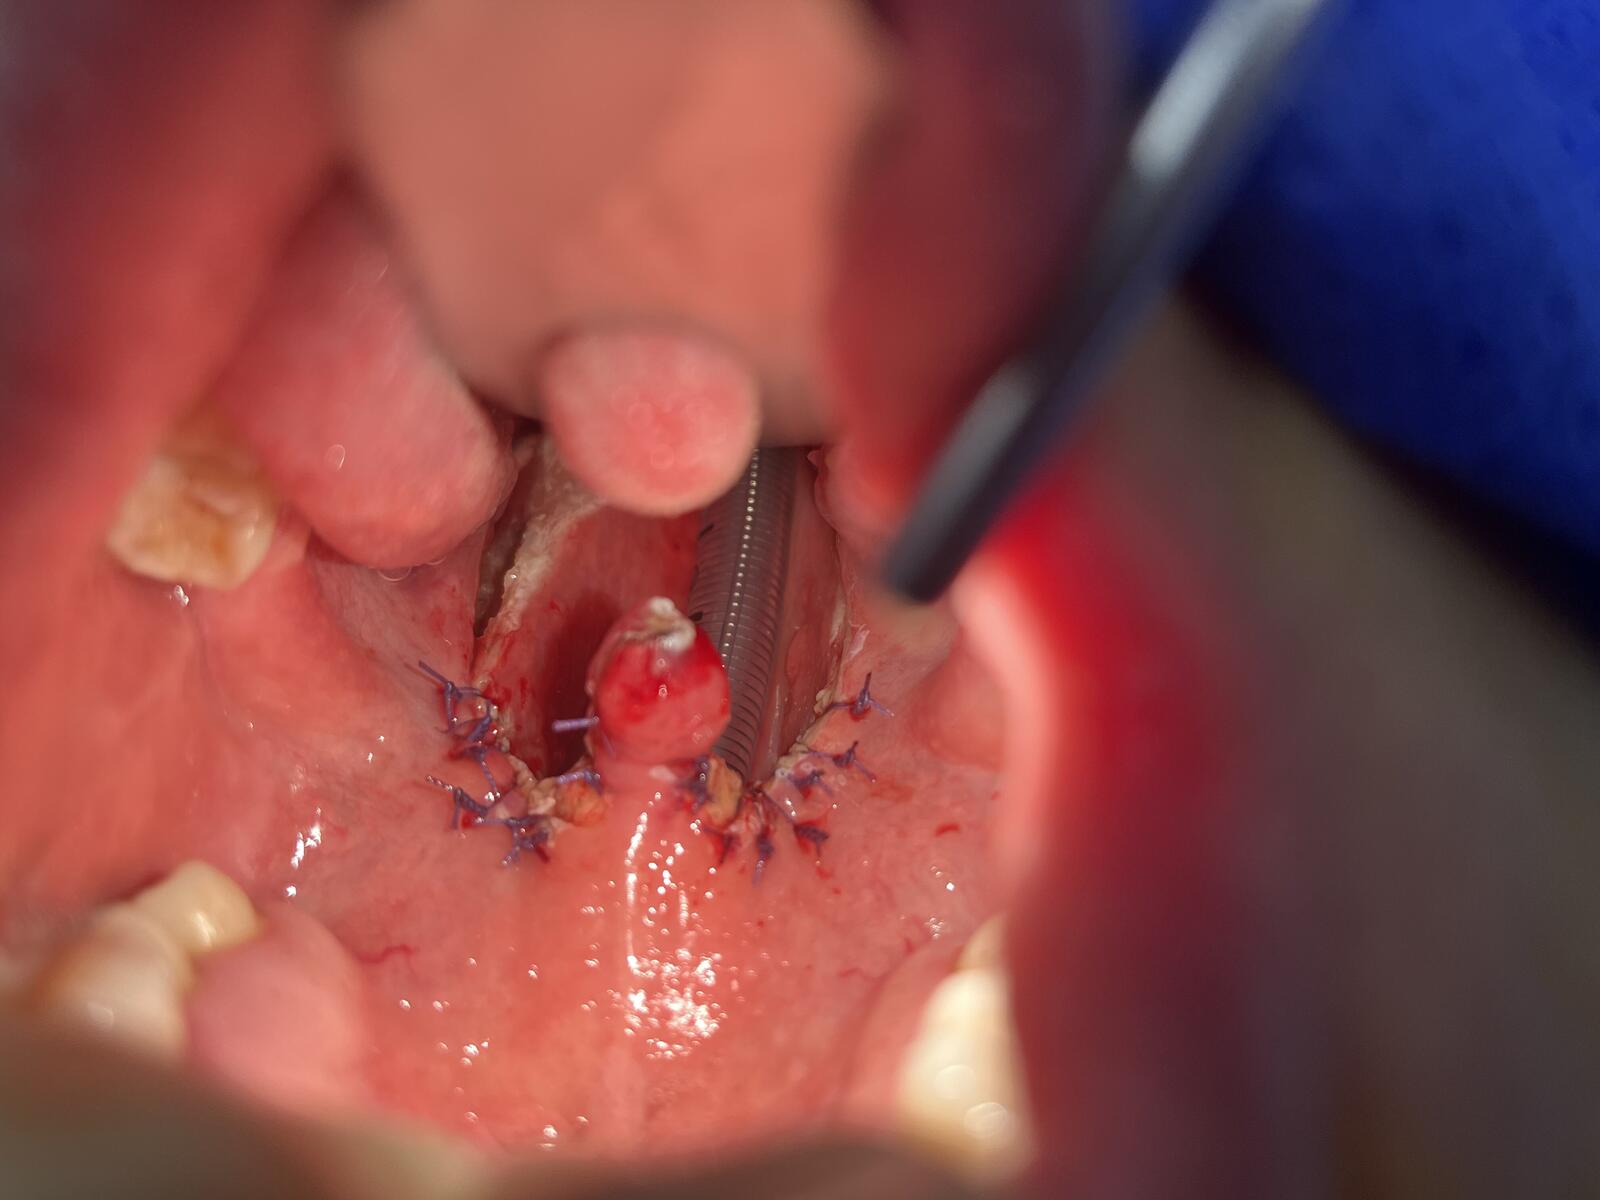

女儿的扁桃体保留双侧下极的1/5

左扁桃体下极保留1/5

切除肥大扁桃体